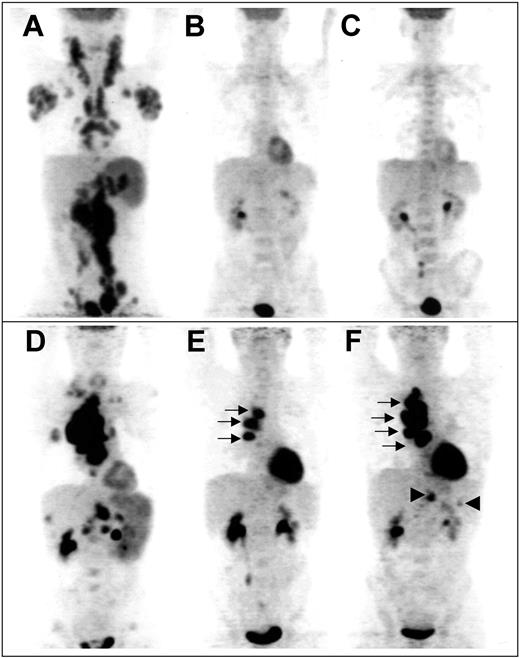

Example of sequential FDG-PET findings in 2 patients. Panels A-C show scans from a patient with truly negative “early PET,” predicting CR. (A) Pretherapeutic scan shows diffuse involvement of jugular chains, axillae, mediastinum, mesenteric chains, spleen, and lateroaortic and iliac chains. No residual uptake is seen after 2 cycles (B) and after 4 cycles (C) of chemotherapy, whereas a medullar uptake is evidenced, due to hematopoietic activation. Panels D-F show scans from a patient with truly positive “early PET,” predicting relapse. (D) Pretherapeutic scan shows a cluster of hypermetabolic nodes in the right pulmonary hilum, supraclavicular and mesenteric nodes, and involvement of the spleen, right lung, liver, and lumbar spine. Three hilar foci persist after 2 cycles (E, arrows); their extent increases after 4 cycles (F, arrows), whereas subdiaphragmatic sites reappear (arrowheads), indicating progression of the disease.